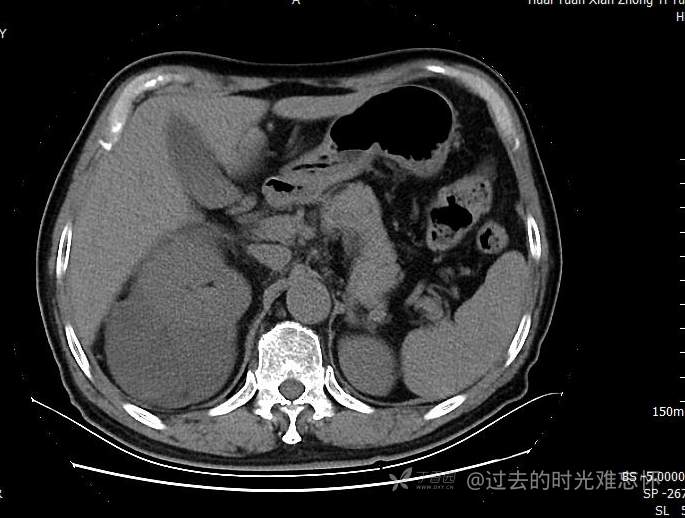

患者性别:男

患者年龄:73岁

主诉:咳嗽1月余。曾有血尿一次。后背部酸痛不适1-2年左右,无明显消瘦。

辅助检查:CT MRI

临床诊断:占位

治疗经过:手术

增强

黏液样脂肪肉瘤 (12)